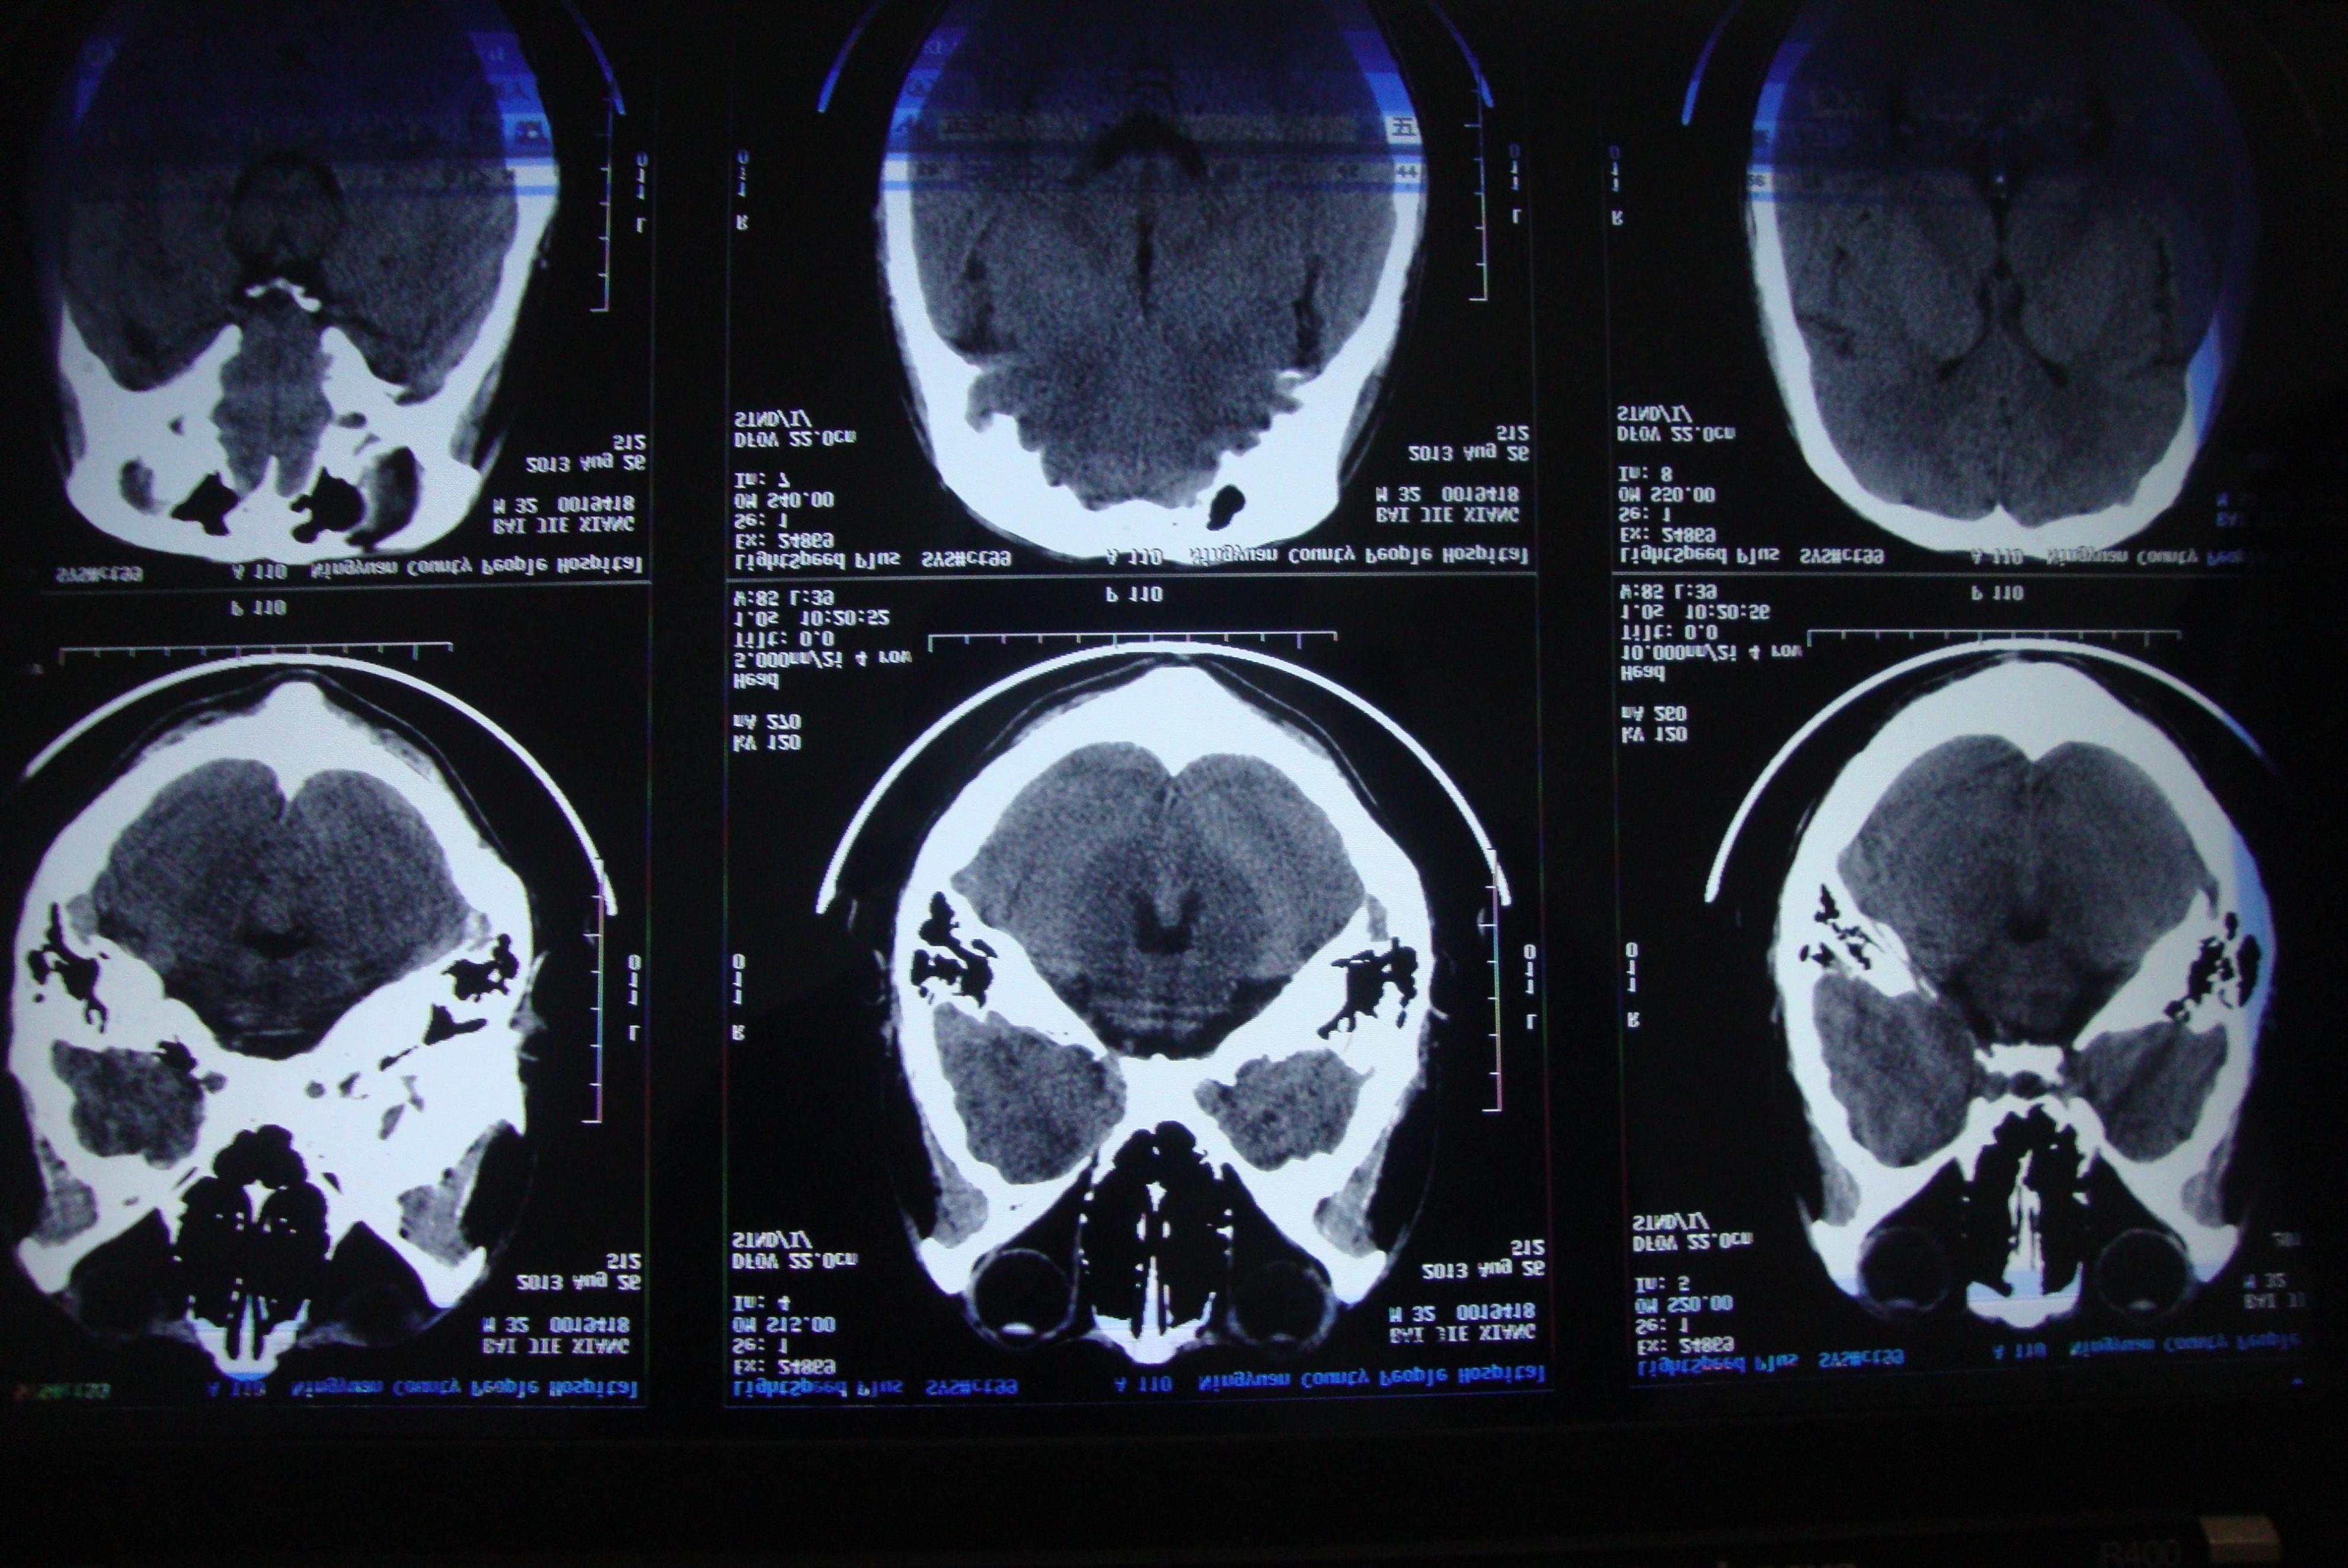

脑萎缩 是老年人常见的生理现象,随着年龄的增长,人体各个器官都会经历一定的退化和功能下降,而 大脑也不例外 。脑萎缩指的是 大脑组织的体积减小 和 神经元数量减少 的现象,这是一种 自然的衰老过程 。

通常是由于神经元的凋亡和突触连接的减少,以及神经纤维的退化所导致的。脑萎缩会影响到大脑的结构和功能,进而对 认知能力、记忆力和日常生活 产生影响。